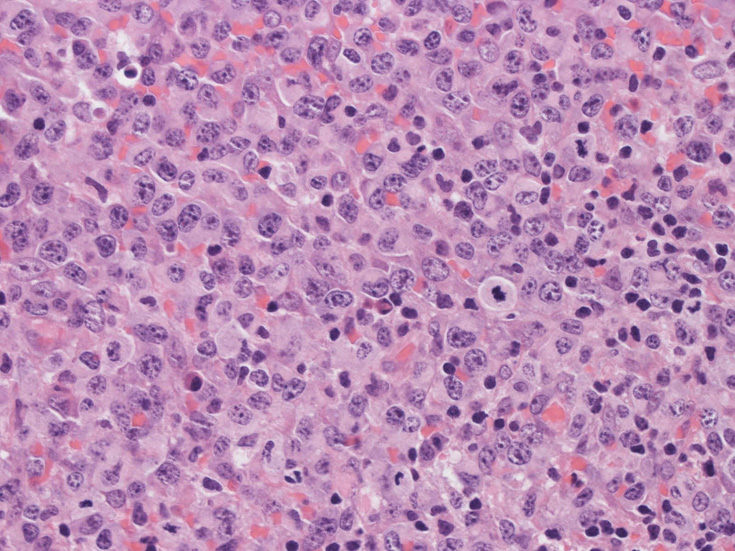

高倍率x400では, 増殖細胞はcentroblastに似て複数の明瞭な核小体をもった淡明な大型類円ないし卵円形核を持っている。核分裂像が多い。この症例では多型はめだたない。典型的な腎臓型のくびれた核を持つ細胞などはない。ALKの形態的variant症例と考えられるが, 化学療法後の再発による影響も否定できない。

腫瘍細胞x400細胞質の豊富な異型細胞核分裂が多いx400